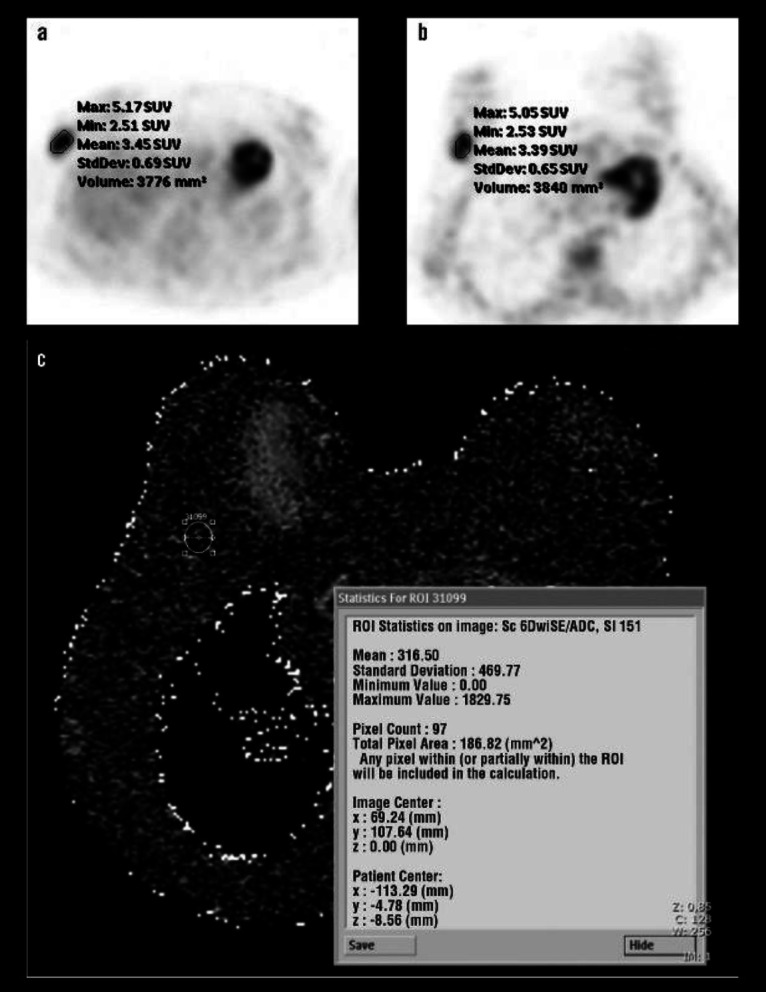

Objectives: Breast carcinoma is the most common type of cancer in females. This study aims to compare fluorine-18-fluorodeoxyglucose (18F-FDG) uptake pattern and apparent diffusion coefficient (ADC) value for the detection of the primary tumour and axillary metastases of invasive ductal breast carcinoma.

Methods: This study included 40 breast carcinoma lesions taken from 39 patients. After staging by positron emission tomography-computed tomography (PET/CT) and diffusion-weighted magnetic resonance imaging (MRI), breast surgery with axillary lymph node dissection or sentinel lymph node biopsy was performed.

Results: Primary lesion detection rate for PET/CT and diffusion-weighted MRI was high with 39 of 40 lesions (97.5%). The sensitivity and specificity for the detection of metastatic lymph nodes in axilla were 40.9%, 88.9%, with 18F-FDG PET/CT scans and 40.9%, 83.3%, for dw-MRI, respectively. No significant correlation was detected between ADC and SUVmax or SUVmax ratios. Estrogen receptor (p=0.007) and progesterone receptor (p=0.036) positive patients had lower ADC values. Tumour SUVmax was lower in T1 than T2 tumour size (p=0.027) and progesterone receptor-positive patients (p=0.029). Tumour/background SUVmax was lower in progesterone receptor-positive patients (p=0.004). Tumour/liver SUVmax was higher in grade III patients (p=0.035) and progesterone receptor negative status (p=0.043).

Conclusions: This study confirmed the high detection rate of breast carcinoma in both modalities. They have same sensitivity for the detection of axillary lymph node metastases, whereas the PET/CT scan had higher specificity. Furthermore, ADC, SUVmax and SUVmax ratios showed some statistical significance among the patient groups according to different pathological parameters.